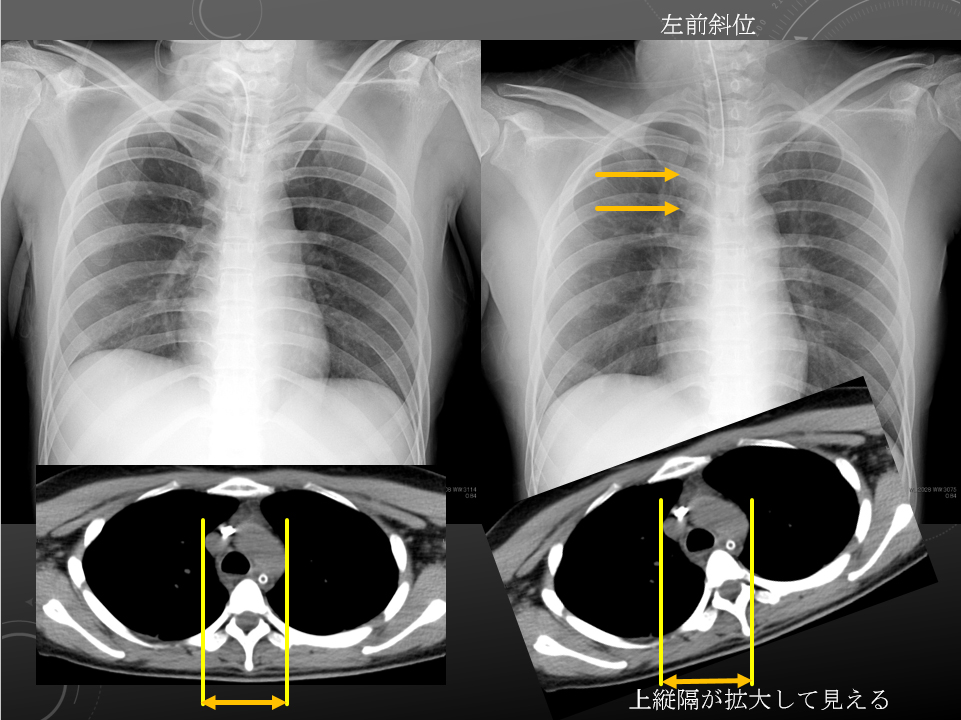

左前斜位